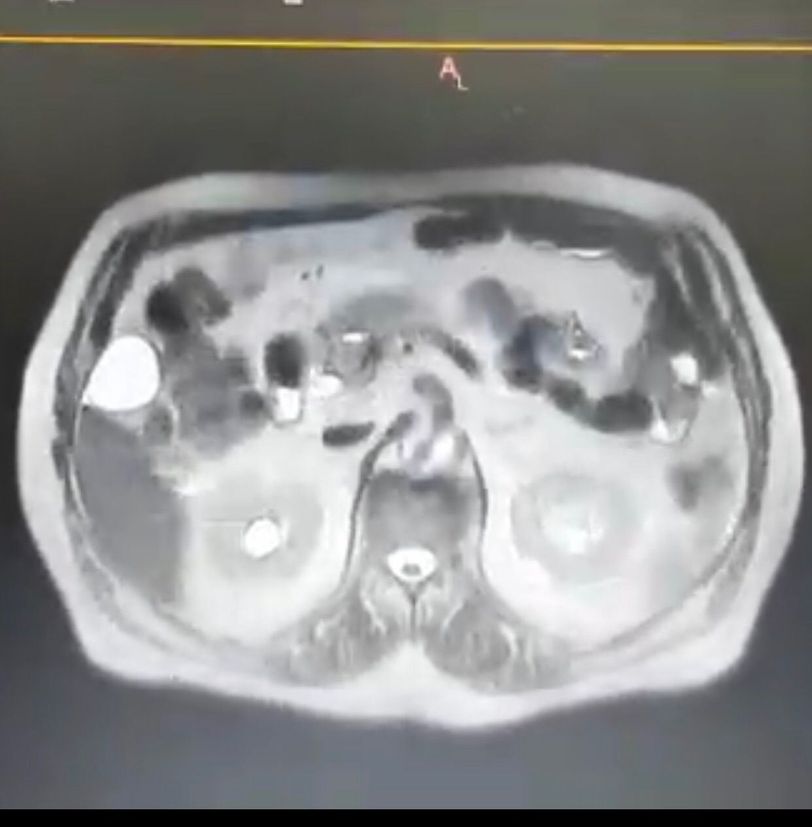

if anyone help me please what is that

He was complaining of inflammation in the pancreas, according to doctors' reports. He had a tumor. Can it be identified in the picture?

Other cuts to cranial will show it better. I couldn't identify that in this section.